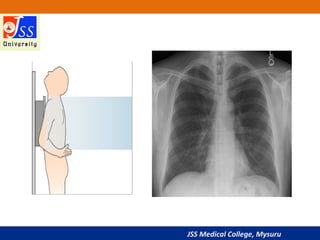

Posterior-anterior (PA) Position

• The standard position for obtaining a routine adult chest

radiograph

• Patient stands upright with the anterior wall of chest placed

against the front of the film

• The shoulders are rotated forward enough to touch the film,

ensuring that the scapulae do not obscure a portion of the lung

fields

• Usually taken with the patient in full inspiration

• The PA film is viewed as if the patient is standing in front of you